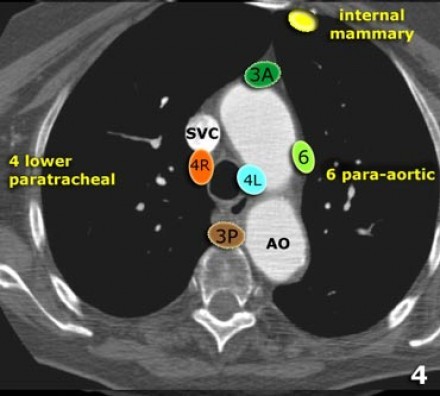

4R. Paratraqueais Inferiores Direitos

Limite superior: intersecção da margem caudal da veia inominada (brachiocefálica esquerda) com a traqueia.

Limite inferior: borda inferior da veia ázigo.

Linfonodos 4R estendem-se para a borda lateral esquerda da traqueia.

Linfonodos paratraqueais 4R

4L. Paratraqueal Inferior Esquerdo

5. Linfonodos Subaórticos